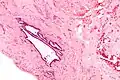

| High magnification micrograph of endosalpingiosis, showing the characteristic cystic spaces lined by a simple epithelium with cilia. H&E stain. | |

It is characterized by cysts with tubal-type epithelium (e.g. ciliated epithelium) surrounded by a fibrous stroma. It is not often associated with hemorrhage.

High mag.